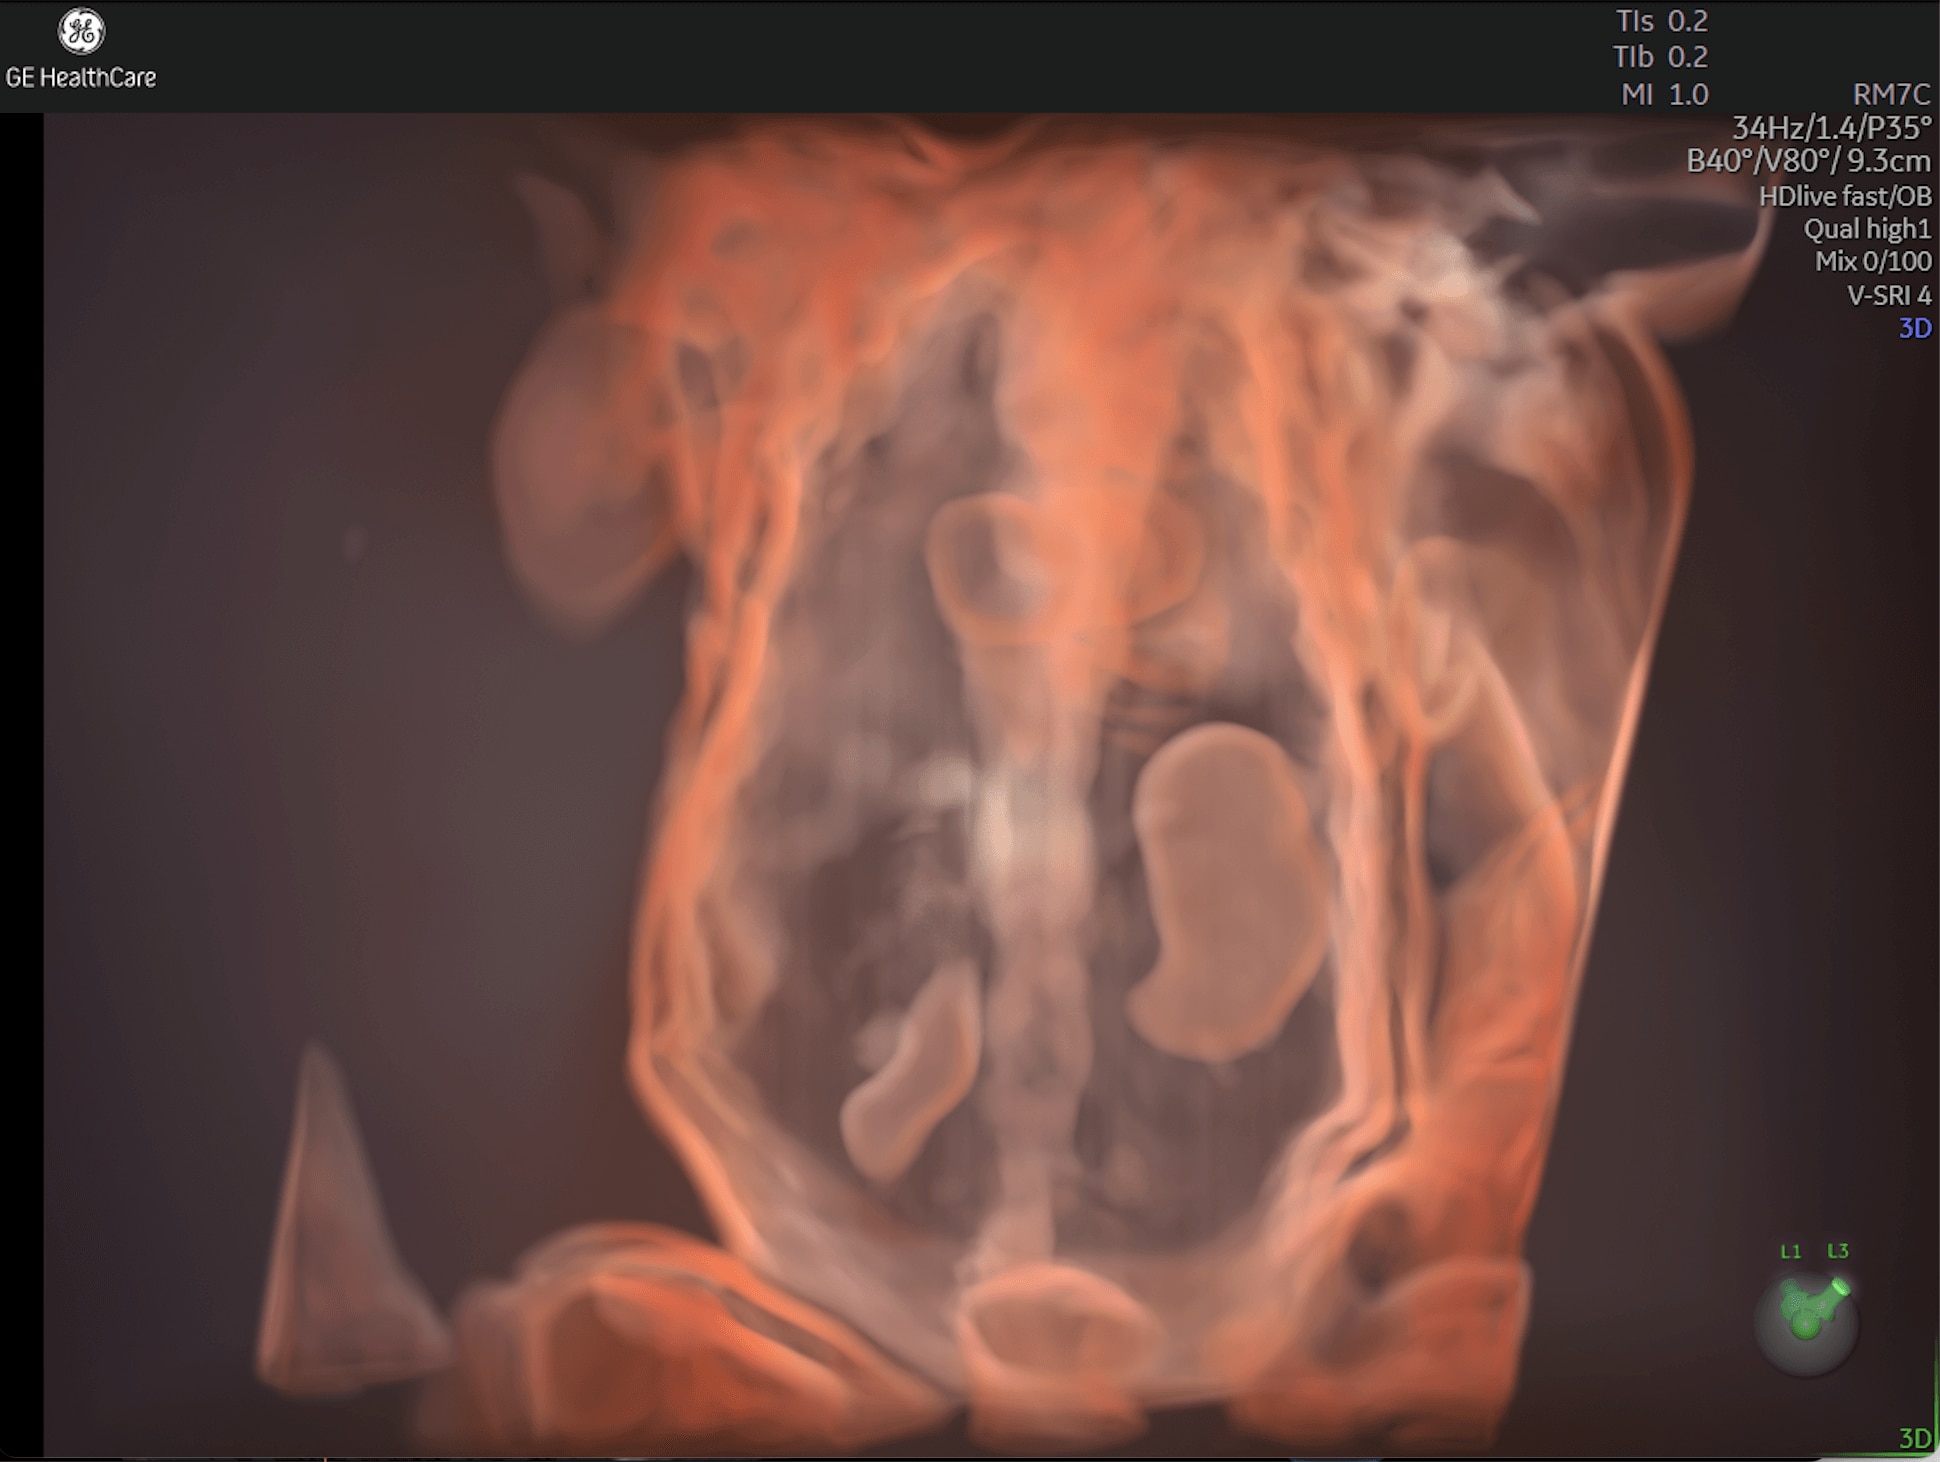

Enhanced Volume Imaging

Deliver next generation 3D/4D & Color images with HDlive Studio+

Unique Probe Technology

Obtain high resolution images with advanced probe technology - eM6C, RIC6-12, and RM7C